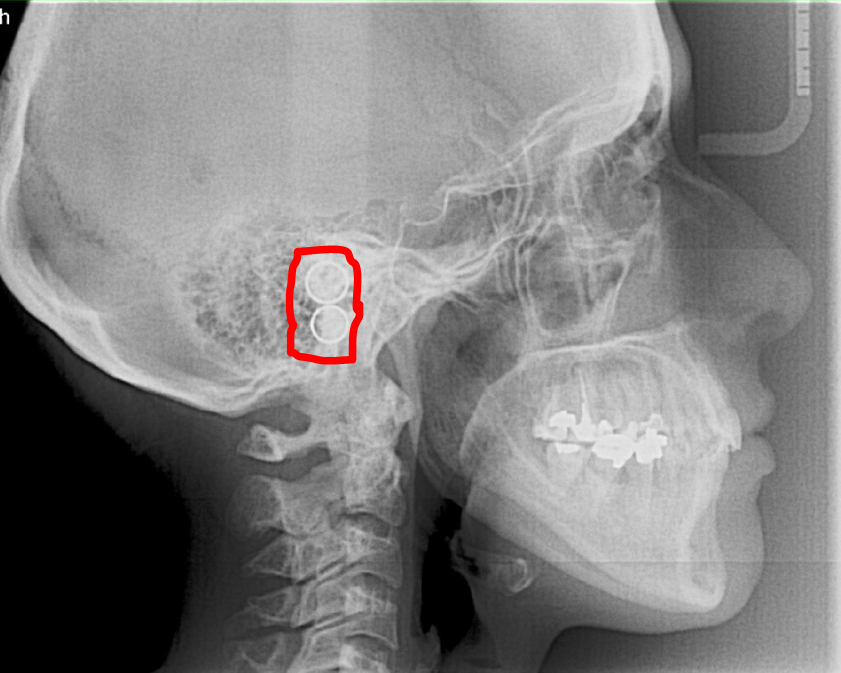

We have attached a PDF file that will help you align the Ear rods for the Ceph. If the reigns look as below image you need to align the ear rods.

In this image, you can see that the rings are not aligned pleaes follow the PDF file attached in this Article. |